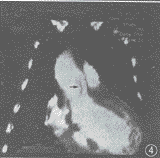

EBCT显示:主动脉升弓部显著扩张,升主动脉与左心室间可见一异常通道,直径约1.5 cm,长约3.0 cm。通道的主动脉端发自左冠状窦外上方,经肺动脉及右心室流出道后方进入左心室。通道和扩张的左冠状窦致右心室流出道受压变形。左心室增大,舒缩功能不良,射血分数为43%(图1~4)。诊断:先天性心血管畸形,主动脉-左心室通道。

图3 通道(↑)与扩张的左冠状窦压迫右心室流出道。前者的心室端开口于左心室

图4 三维曲面重建清淅显示通道(↑)及周围解剖关系